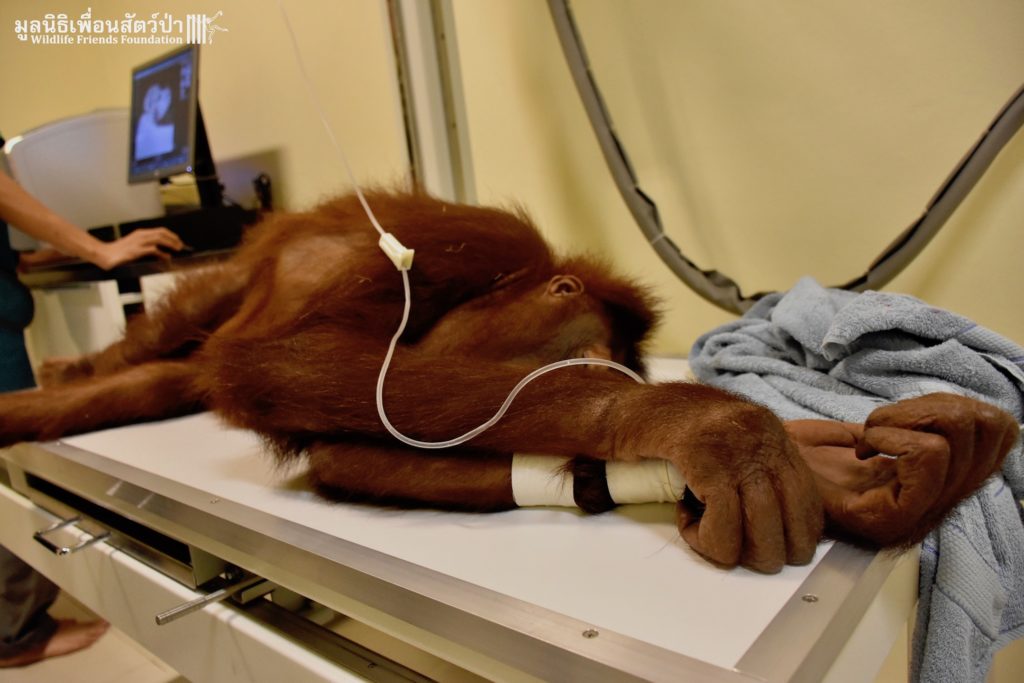

WFFT’s resident great apes, Maggie and Chico the critically endangered orangutans, are now much closer to their wonderful new home. We have moved them from their old night enclosure to a new side enclosure connected to the new huge open forest area we have created for them. During the move they made a pit stop at the WFFT Wildlife Hospital so a full health check could be performed, including a full body x-ray which was performed for the first time. This whole operation would have not been possible without the kindness and support of Mr. Mike Beets, so thank you Mike!!! And a great big thank you to the International Primate Protection League. All the team at WFFT are waiting in excitement to see these very special apes out exploring very soon. Watch this space over the coming days for an update about their first exploration expedition around their new home.